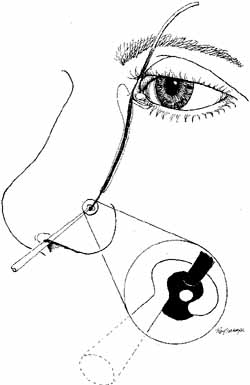

Fig. 25 A and B. Ritleng probe with hollow lumen and stylette used while passing the probe. A

slit exits along the side to remove prolene lead attached to Silastic

tubing distally.

Fig. 25 A and B. Ritleng probe with hollow lumen and stylette used while passing the probe. A

slit exits along the side to remove prolene lead attached to Silastic

tubing distally.

As for the monocanalicular stents, our preference is to use the Ritleng

probe for passage. This hollow probe has a directed groove at the distal

tip (Fig. 25A and 25B). The prolene portion on the Silastic tubing is fed down the probe

and recovered from the nose (Fig. 26). Sometimes the directional groove will lead the prolene portion

directly out the nostril. It is helpful to feed a majority of the prolene

down the probe to facilitate distal recovery. The Ritleng hook, Crawford

hook, or myringotomy forceps can be utilized to retrieve the prolene

portion from the nose. If any trouble is encountered retrieving

the prolene feeder, the surgeon should feel for the Ritleng probe and

hook it. Once the hook is around the probe, the probe should be rotated 180 degrees

because this will position the distal opening of the probe

posteriorly. In addition, the probe should be slightly withdrawn. The

hook will engage the prolene feeder when the hook is pulled anteriorly. It

is important to note that the prolene thread has two portions, a

light blue section and a dark blue section. The darker portion has

a thicker diameter. When all the dark prolene has been inserted down the

probe, the light blue, thinner portion should be passed outside the

slit on the side of the probe. Simultaneously, the probe should be removed

proximally from the nasolacrimal system. |